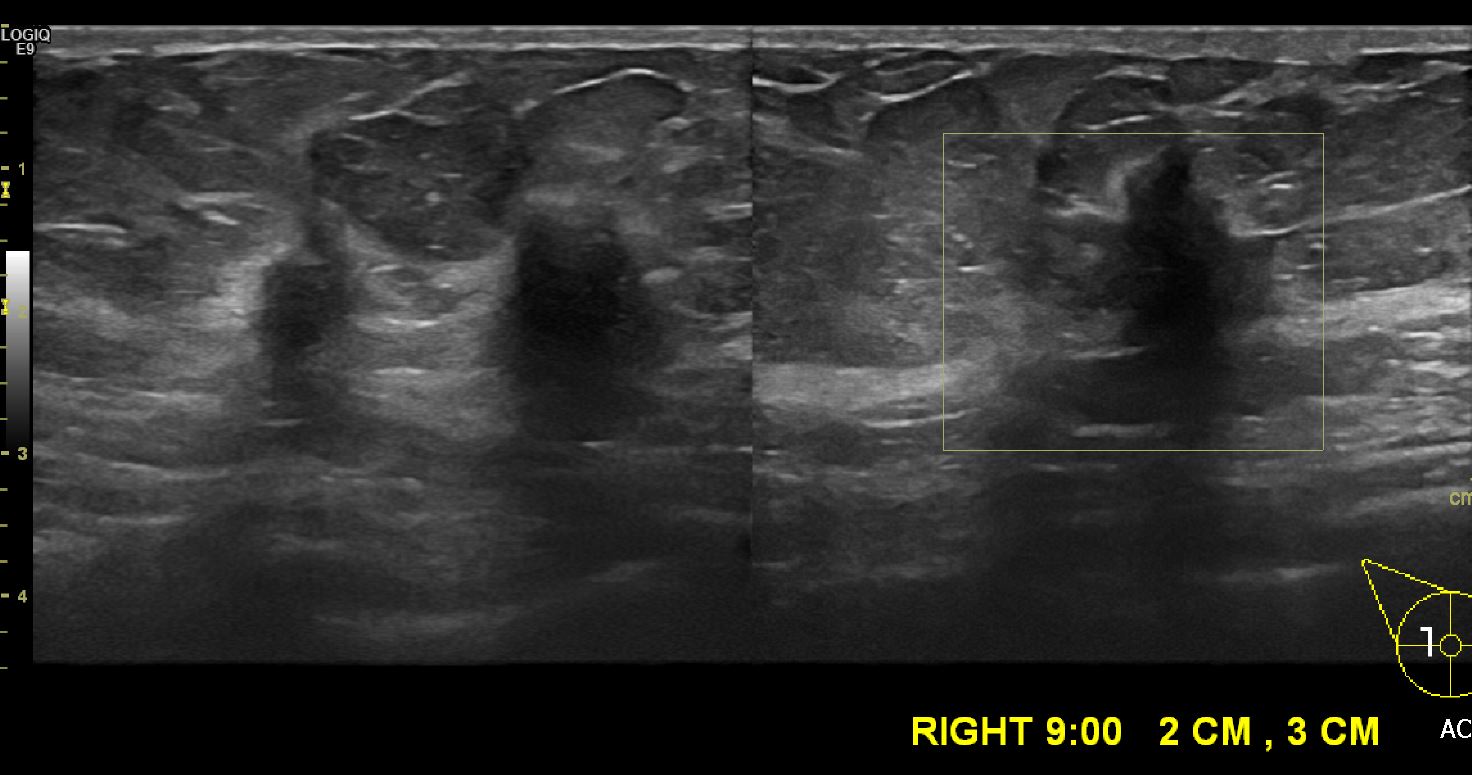

건강 검진상 이상 소견으로 내원하신 60대 여성분으로  우측 9시 방향 2~3 cm 거리의

의심스러운 혹 중심핵생검 시행하여 우측 침윤성 유관암 진단 되었습니다.